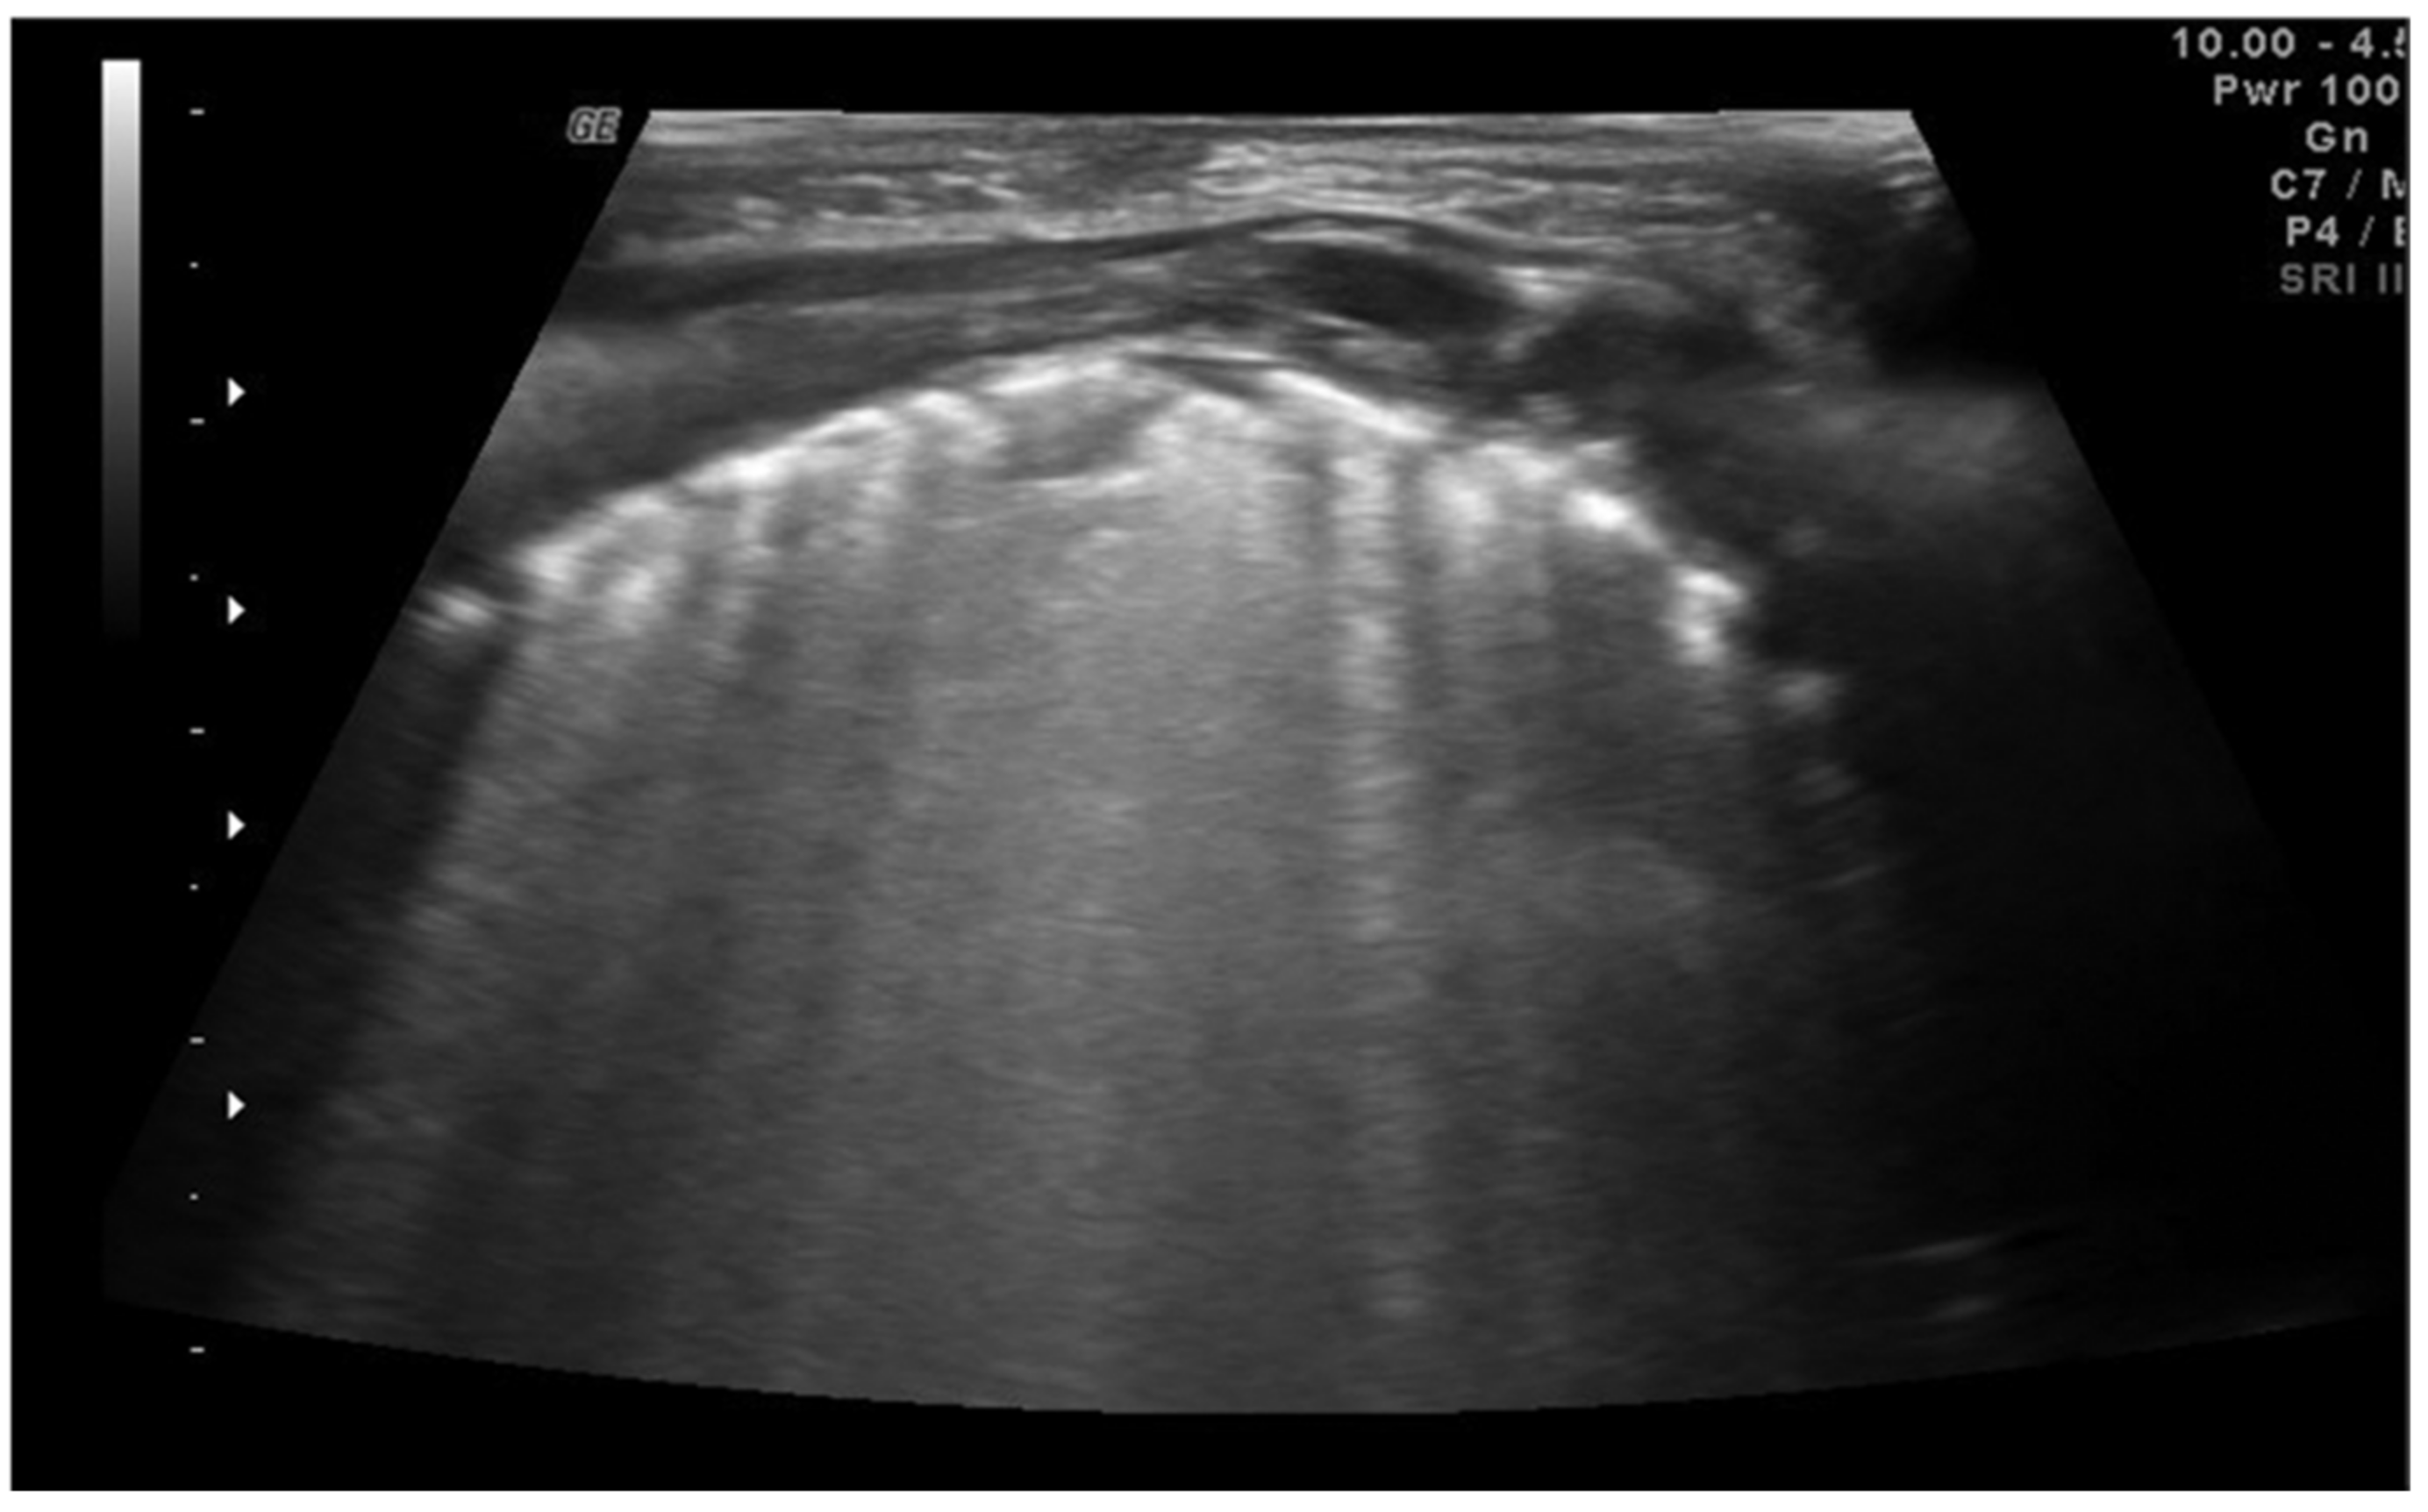

In community-acquired pneumonia (CAP), the main ultrasound findings are consolidations that appear as hypoechoic areas with evidence of an air bronchogram within and an ecostructural “liver pattern,” with clear margins (indicating a lobar consolidation) or surrounded by confluent B-lines (Figure 7) [6].

Figure 7.

Pneumonia. Hypoechoic areas with a liver pattern inside configuring a consolidation. Air bronchogram is visible.

The liver-like ultrasound appearance, which defines the hepatization of the lung, is consequent to the filling of the alveoli with an inflammatory and purulent material that determines a solid and isoechogenic appearance of the lung. Frequently within the consolidations, it is possible to observe a fine hyperechogenic arborescent pattern that defines the air bronchogram due to the presence of air remaining inside the small bronchioles. The air bronchogram typical of pneumonic consolidations is defined as dynamic due to the possibility of observing the air move back and forth with the breaths, a testament to their patency. This ultrasound sign differs from the static air bronchogram, in which air movement is not observable, typical of atelectasis [38].